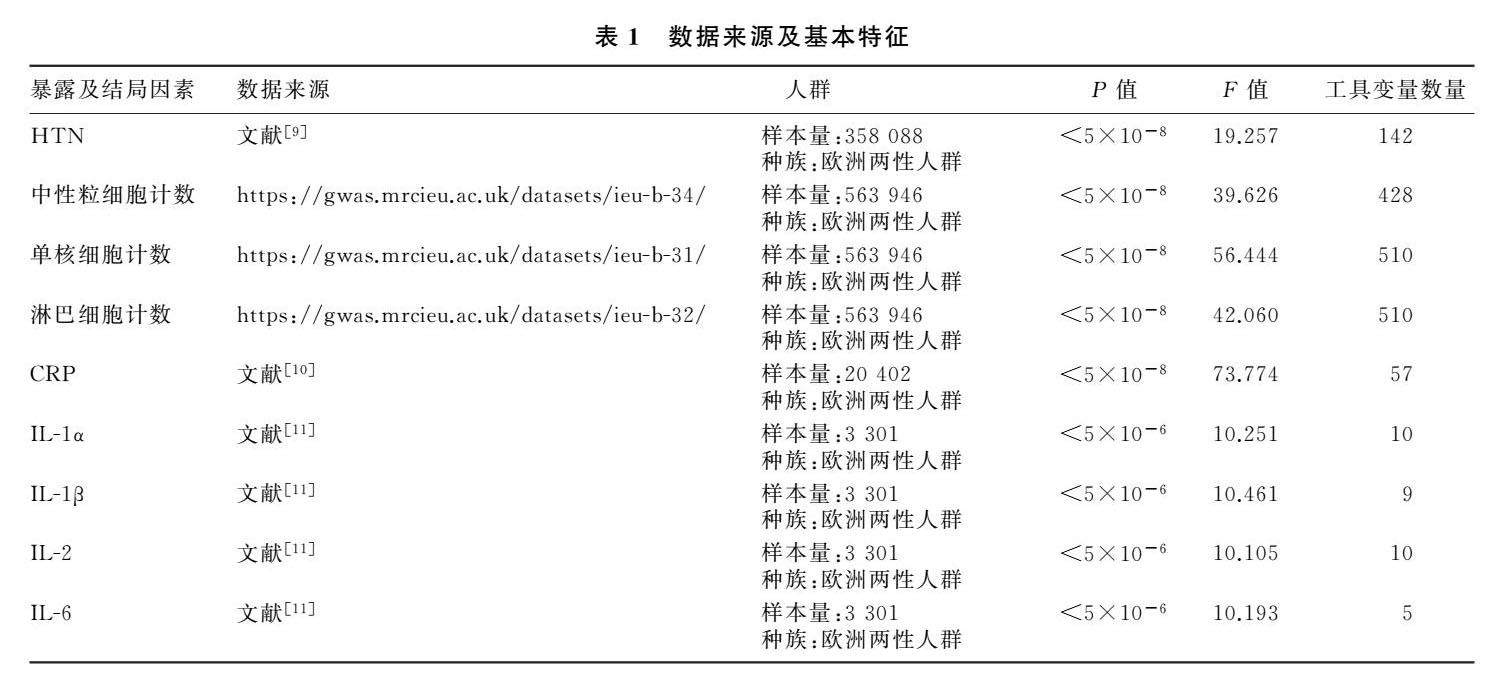

论著 | 外周炎症与原发性高血压相关性的孟德尔随机化分析

论著 | 外周炎症与原发性高血压相关性的孟德尔随机化分析